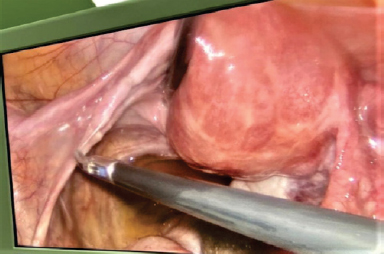

In our clinical case, according to the results of MRI of pelvic organs, the 38-year old patient had a cyst in posterior cul-de-sac with hemorrhagic or high-protein contents, and also the left ovary was not visible. During the laparoscopy an autoamputation of the left uterine adnexa due to torsion was found, as well as presence of necrotizing lesion in posterior cul-de-sac. Thus, laparoscopy is the only reliable method for diagnosing and treating adnexal torsion.